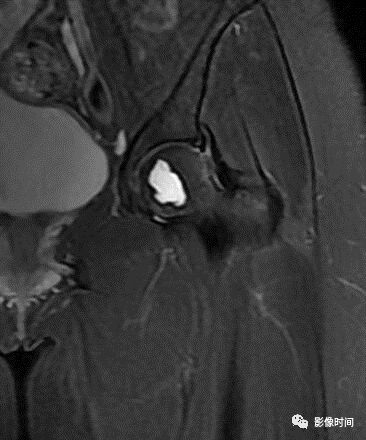

九、瘤周水肿

肿瘤周边的骨髓水肿表现为 T1WT 低信号和 T2WI、STIR 高信号边界模糊的片状影,软组织肿块邻近的正常软组织成分,尤其是肌肉内亦可出现水肿,表现为肿块周围沿肌束方向分布的边界模糊的片状或羽毛状影,有时可连成片。瘤周水肿常见于恶性肿瘤(图 58),但也可见于某些良性肿瘤如软骨母细胞瘤(图 59)、骨样骨瘤和骨嗜酸性肉芽肿(图 60)等。

图 58   瘤周水肿:骨肉瘤

图 59 瘤周水肿:软骨母细胞瘤

图 60  瘤周水肿:骨嗜酸性肉芽肿